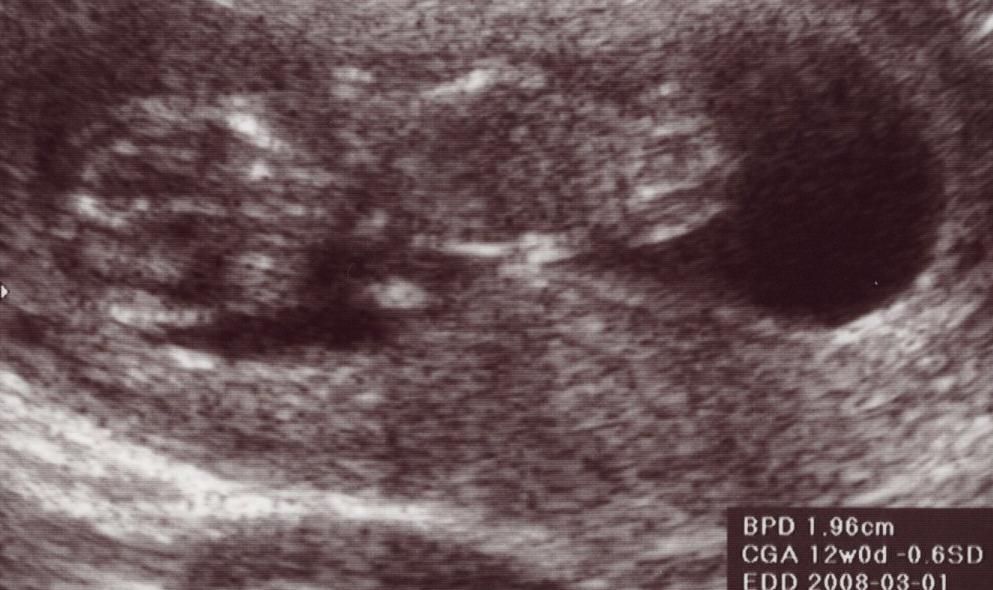

仕事の都合で9w0dには行けず、今日になってしまった。

今、大体3ヶ月半目。